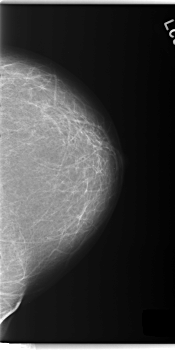

C_0143_1.RIGHT_CC

LEFT_CC LINES 5944 PIXELS_PER_LINE 2960 BITS_PER_PIXEL 12 RESOLUTION 50 NON_OVERLAY